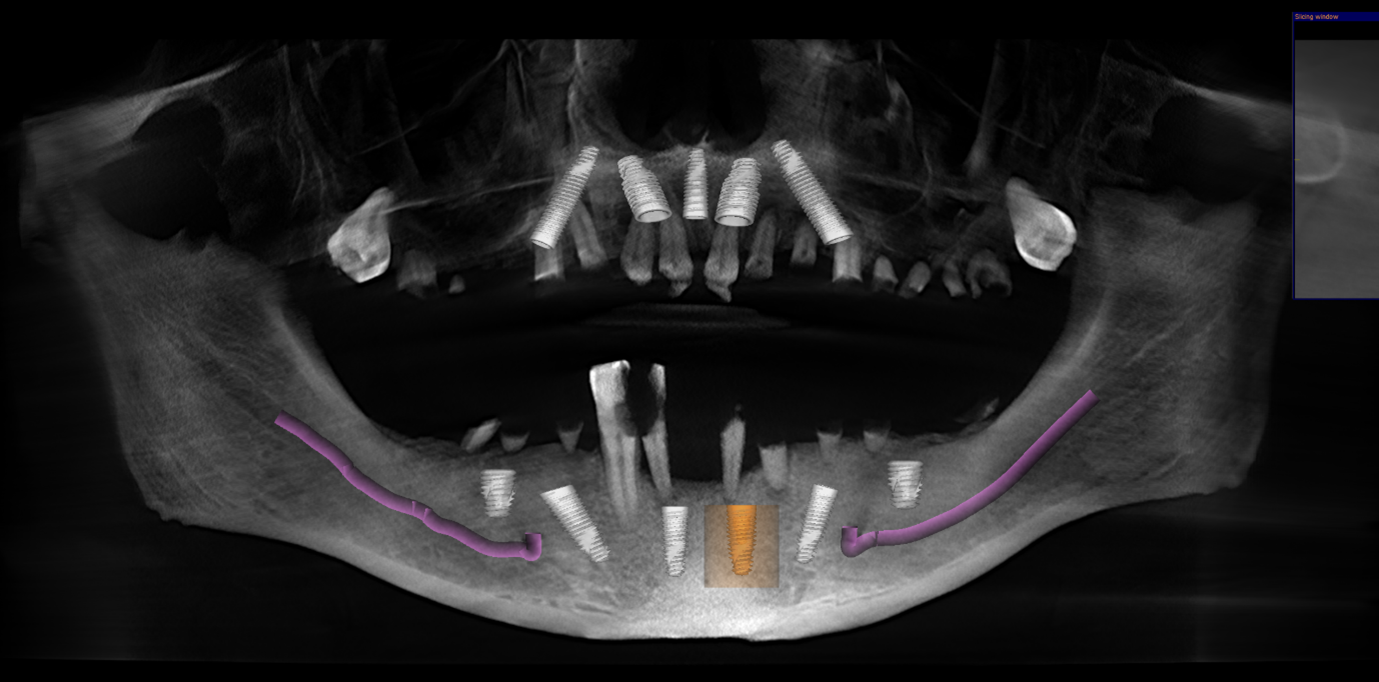

• CBCT scan

• digital implant planning records

These records helped us carefully assess bone levels, gum health, and implant positions.

xAlthough the patient had moderate bone loss in some areas and signs of old chronic abscesses, his overall bone quality was still suitable for implants. There was no active pus or severe infection at the time of treatment.

After discussing all options, the plan was to provide the patient with full arch fixed implant bridges.

The treatment included:

• removal of the failing teeth

• keeping the upper wisdom teeth, as they were buried under the gum and not causing any problems

• bone grafting where needed

• use of CGF (Concentrated Growth Factors) from the patient’s own blood to support healing

• placement of 5 implants in the upper jaw

• placement of 6 implants in the lower jaw

• insertion of temporary fixed teeth on the same day

Because good implant stability was achieved during surgery, the patient was able to receive fixed temporary teeth very quickly.

She explains that detailed CBCT planning was one of the most important parts of the case, as precise planning helps reduce risk and supports long-term success.